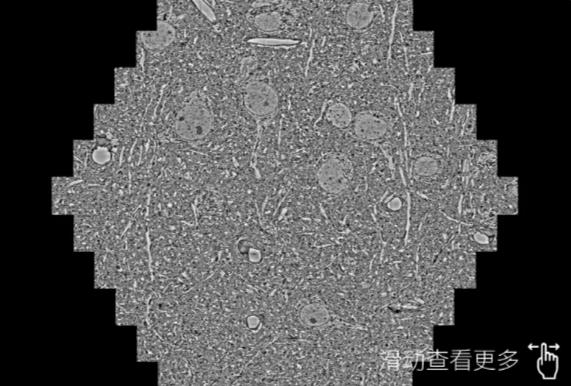

鼠脑切片。左图使用黑河蔡司黑河扫描电镜MultiSEM706对165μmx143pm面积区域成像,耗时仅需1.5秒。右图为鼠脑切片中30μm区域放大效果。样品由芝加哥大学B.Kasthuri提供。

使用蔡司高速黑河扫描电镜MultiSEM对1mm²人脑皮层组织进行高分辨成像,并对其中的各种细胞结构进行三维重构分析。左图展示了2x3mm²组织平面中锥体神经元的三维重构效果。右图显示了局部体积神经元三维重构。图像由哈佛大学chtman实验室提供,渲染图由D. Berger 制作。